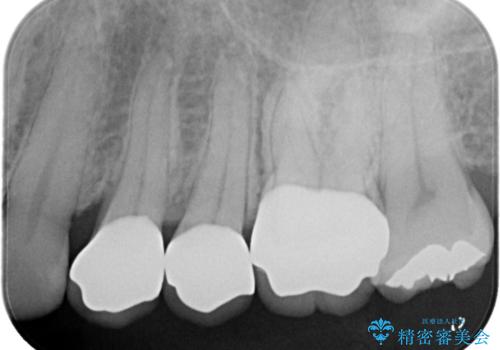

- 歯に穴が開くような虫歯があり銀歯の適合も悪く虫歯になっていたので、虫歯を除去後オールセラミッククラウンで治療を行いました。

左上5、6番の間に隙間もあったのでオールセラミッククラウンで隙間も閉じました。

歯に穴が開くような虫歯があり、銀歯と歯の堺に隙間があり(適合が悪い)そこが虫歯になっていたので適合良く(歯と被せ物の間に隙間が無い)作れるオールセラミッククラウンで治療を行いました。